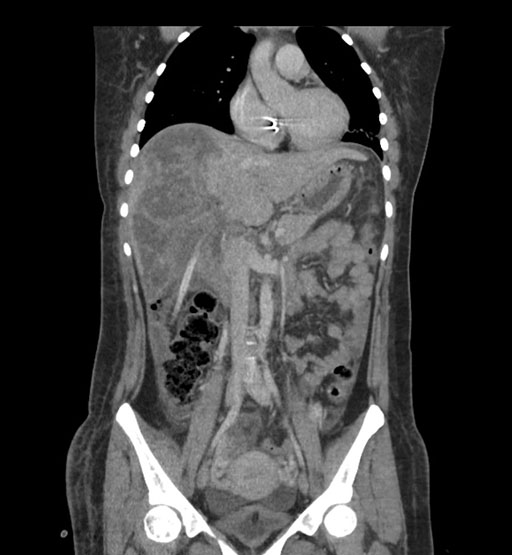

Coronal Arterial

Coronal Venous

Imaging analysis

Based on initial findings, which issue(s) would you be most concerned about?